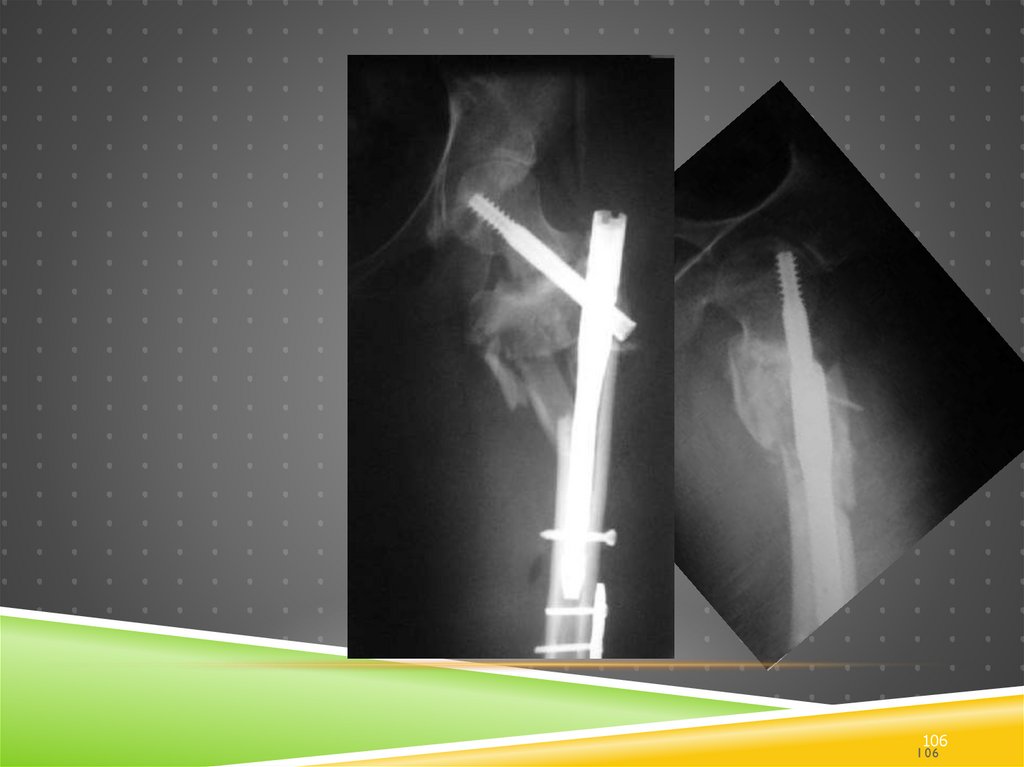

105.

28

Еще один пропущенный # проксимального

отдела

105

106.

106